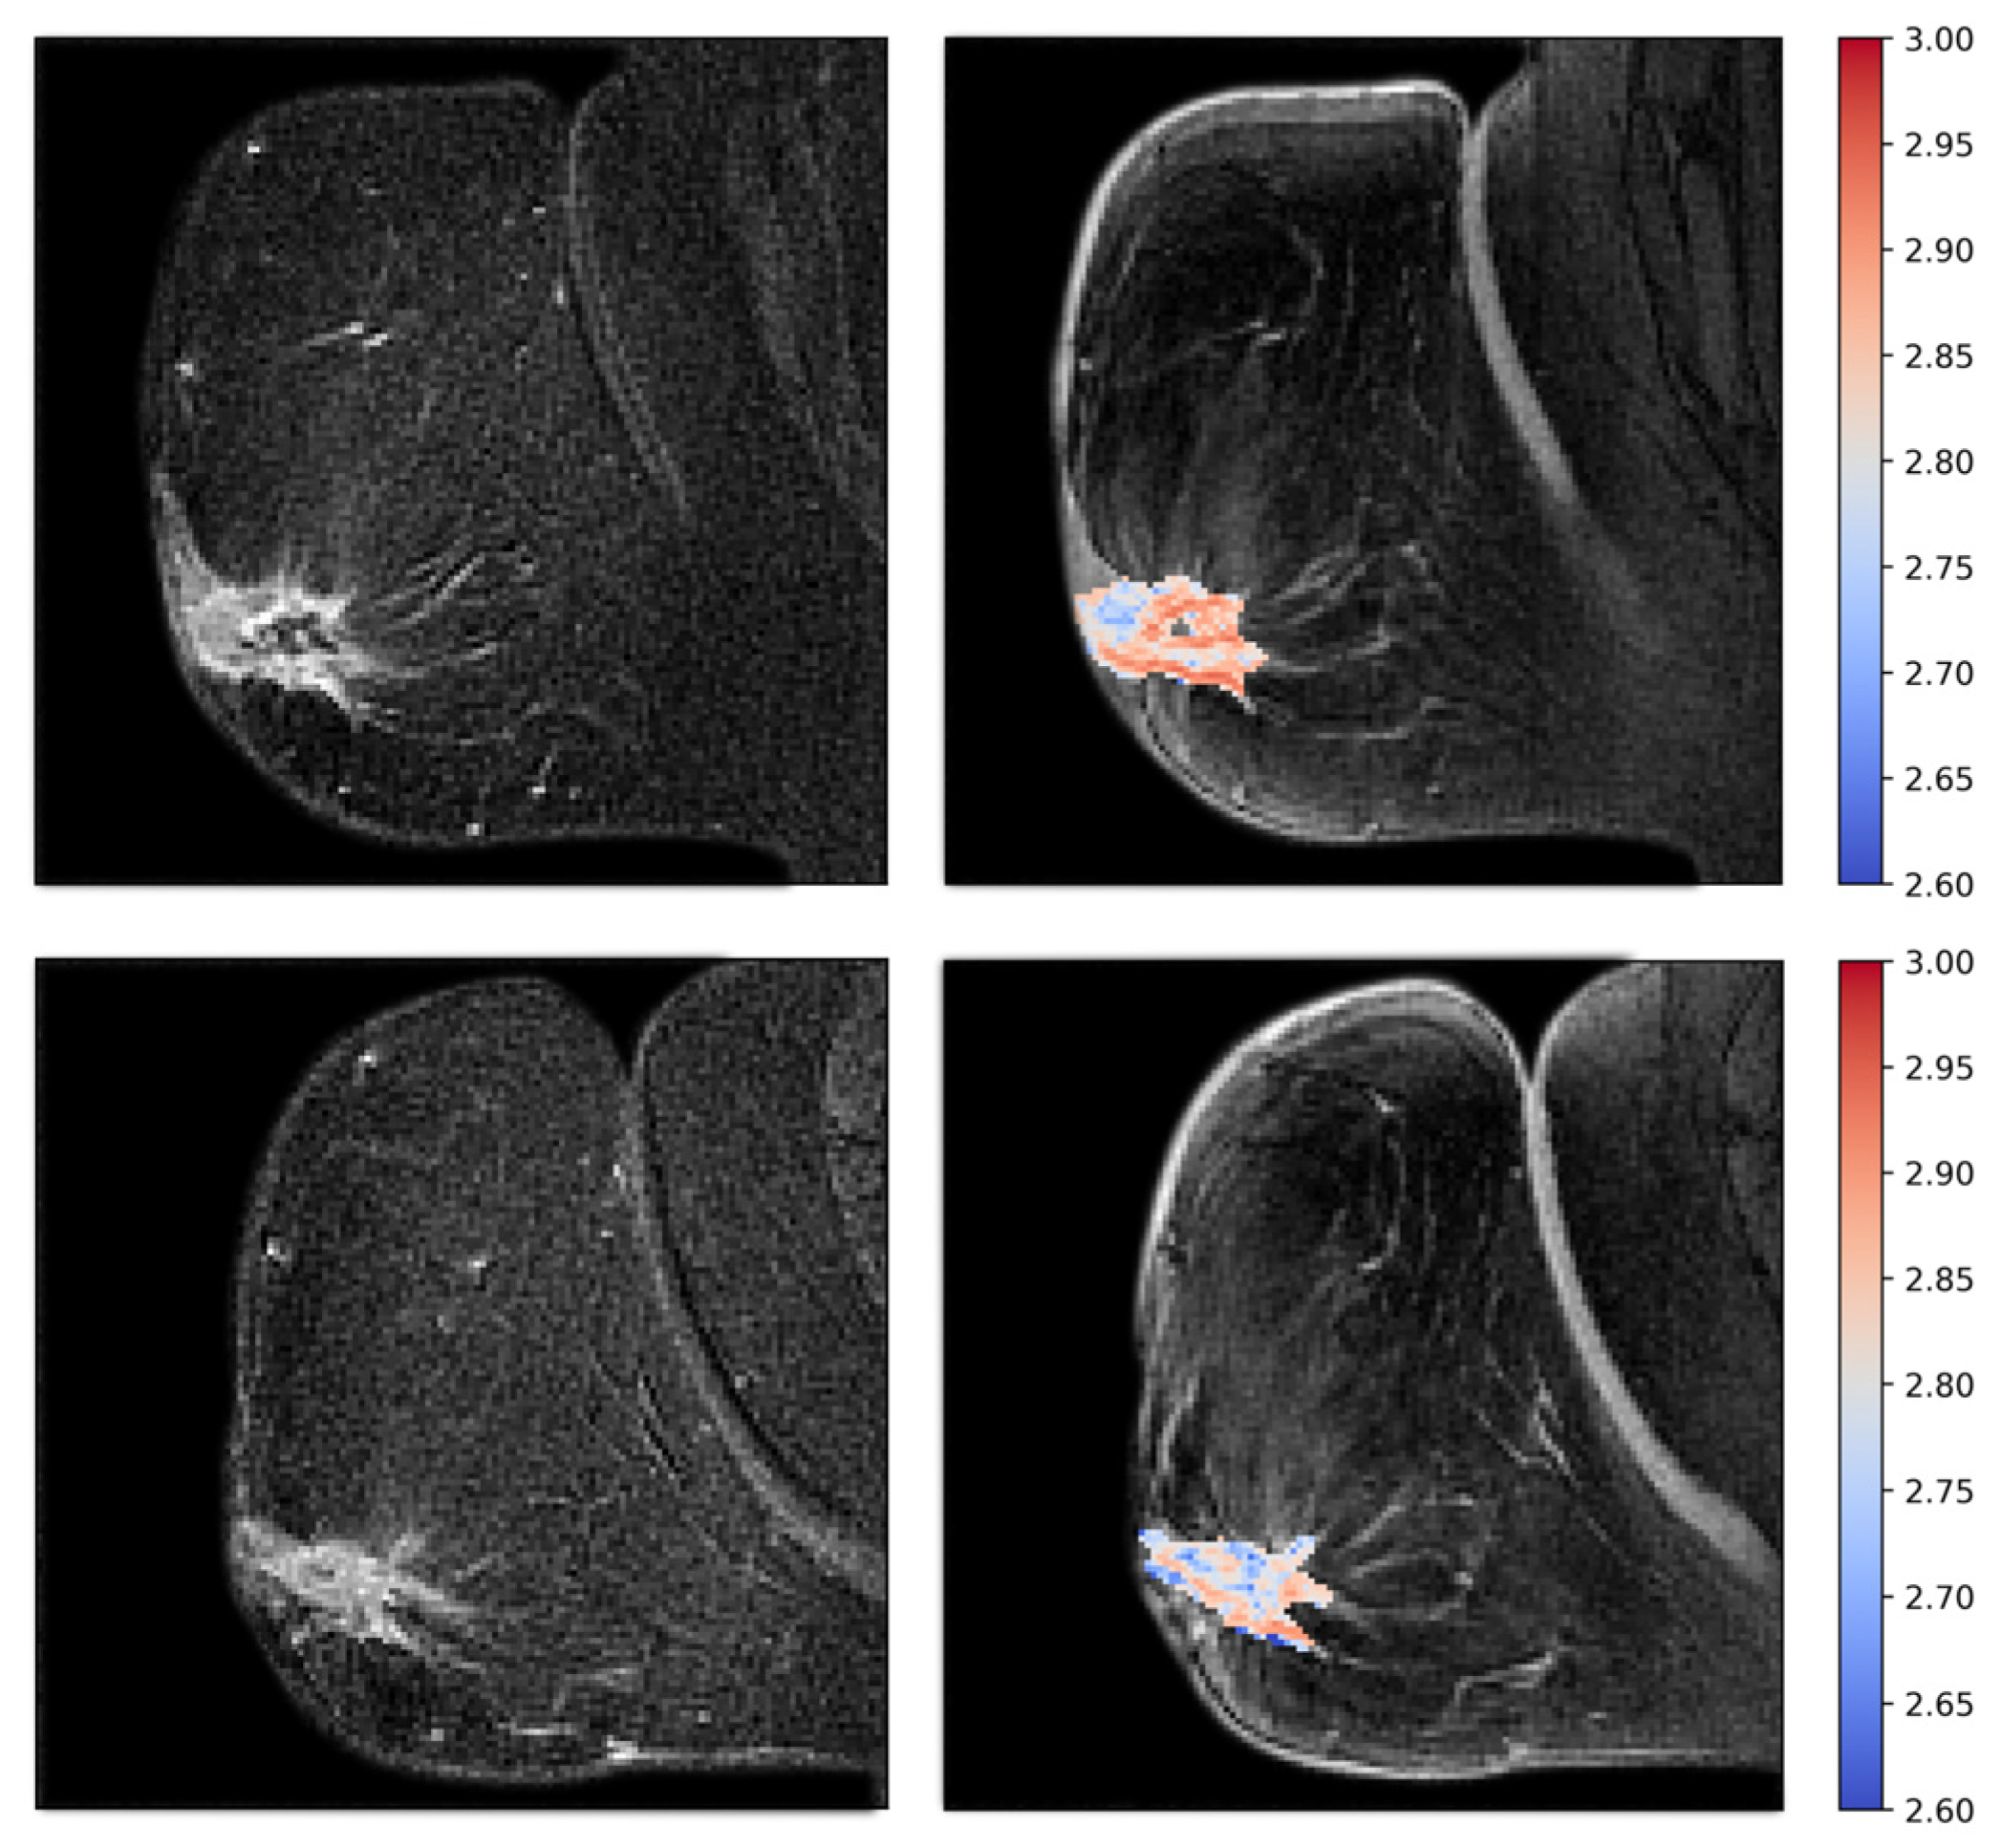

Figure 6.

Patient treated with bevacizumab showing intermediate pre-treatment fractal dimension (top), with a significant increase in fractal dimensionality after one week of treatment (bottom). The fractal dimension maps are shown to the right as colored overlays on T2-weighted images. To the left are the subtraction images that the fractal dimension is calculated from.

Figure 7.

Patient treated with bevacizumab, showing high pretreatment fractal dimension (top), with a significant reduction after one week of treatment (bottom). Fractal dimension maps are shown to the right, and subtraction images are shown to the left.